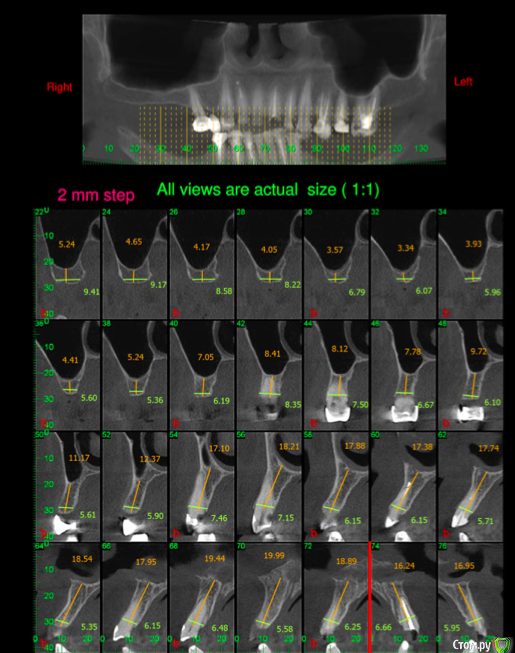

Sir Edward'S Опубликовано 23 марта, 2019 Поделиться Опубликовано 23 марта, 2019 Обратилась пациентка с болезнью паркинсона на 3 стадии ( первый случай в моей практике )Как помочь пациентке ? Ссылка на комментарий